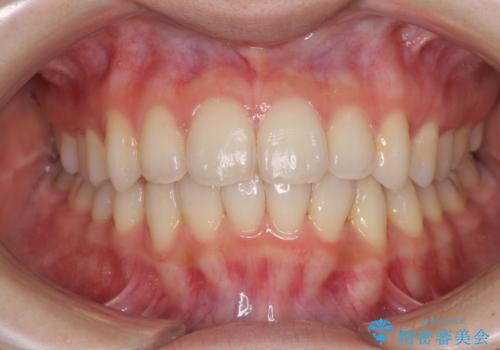

奥歯の咬み合わせを改善したいため、治療期間が長くなりましたが、患者様には辛抱強くお付き合いいただきました。

上下の正中を合わせることもでき、患者様には大変満足していただきました。